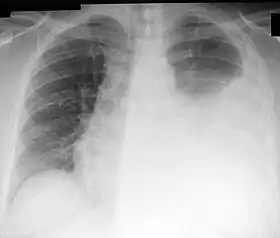

![]() Chest X-ray showing a left-sided pleural effusion (right side of image). This can be treated with thoracentesis. | |